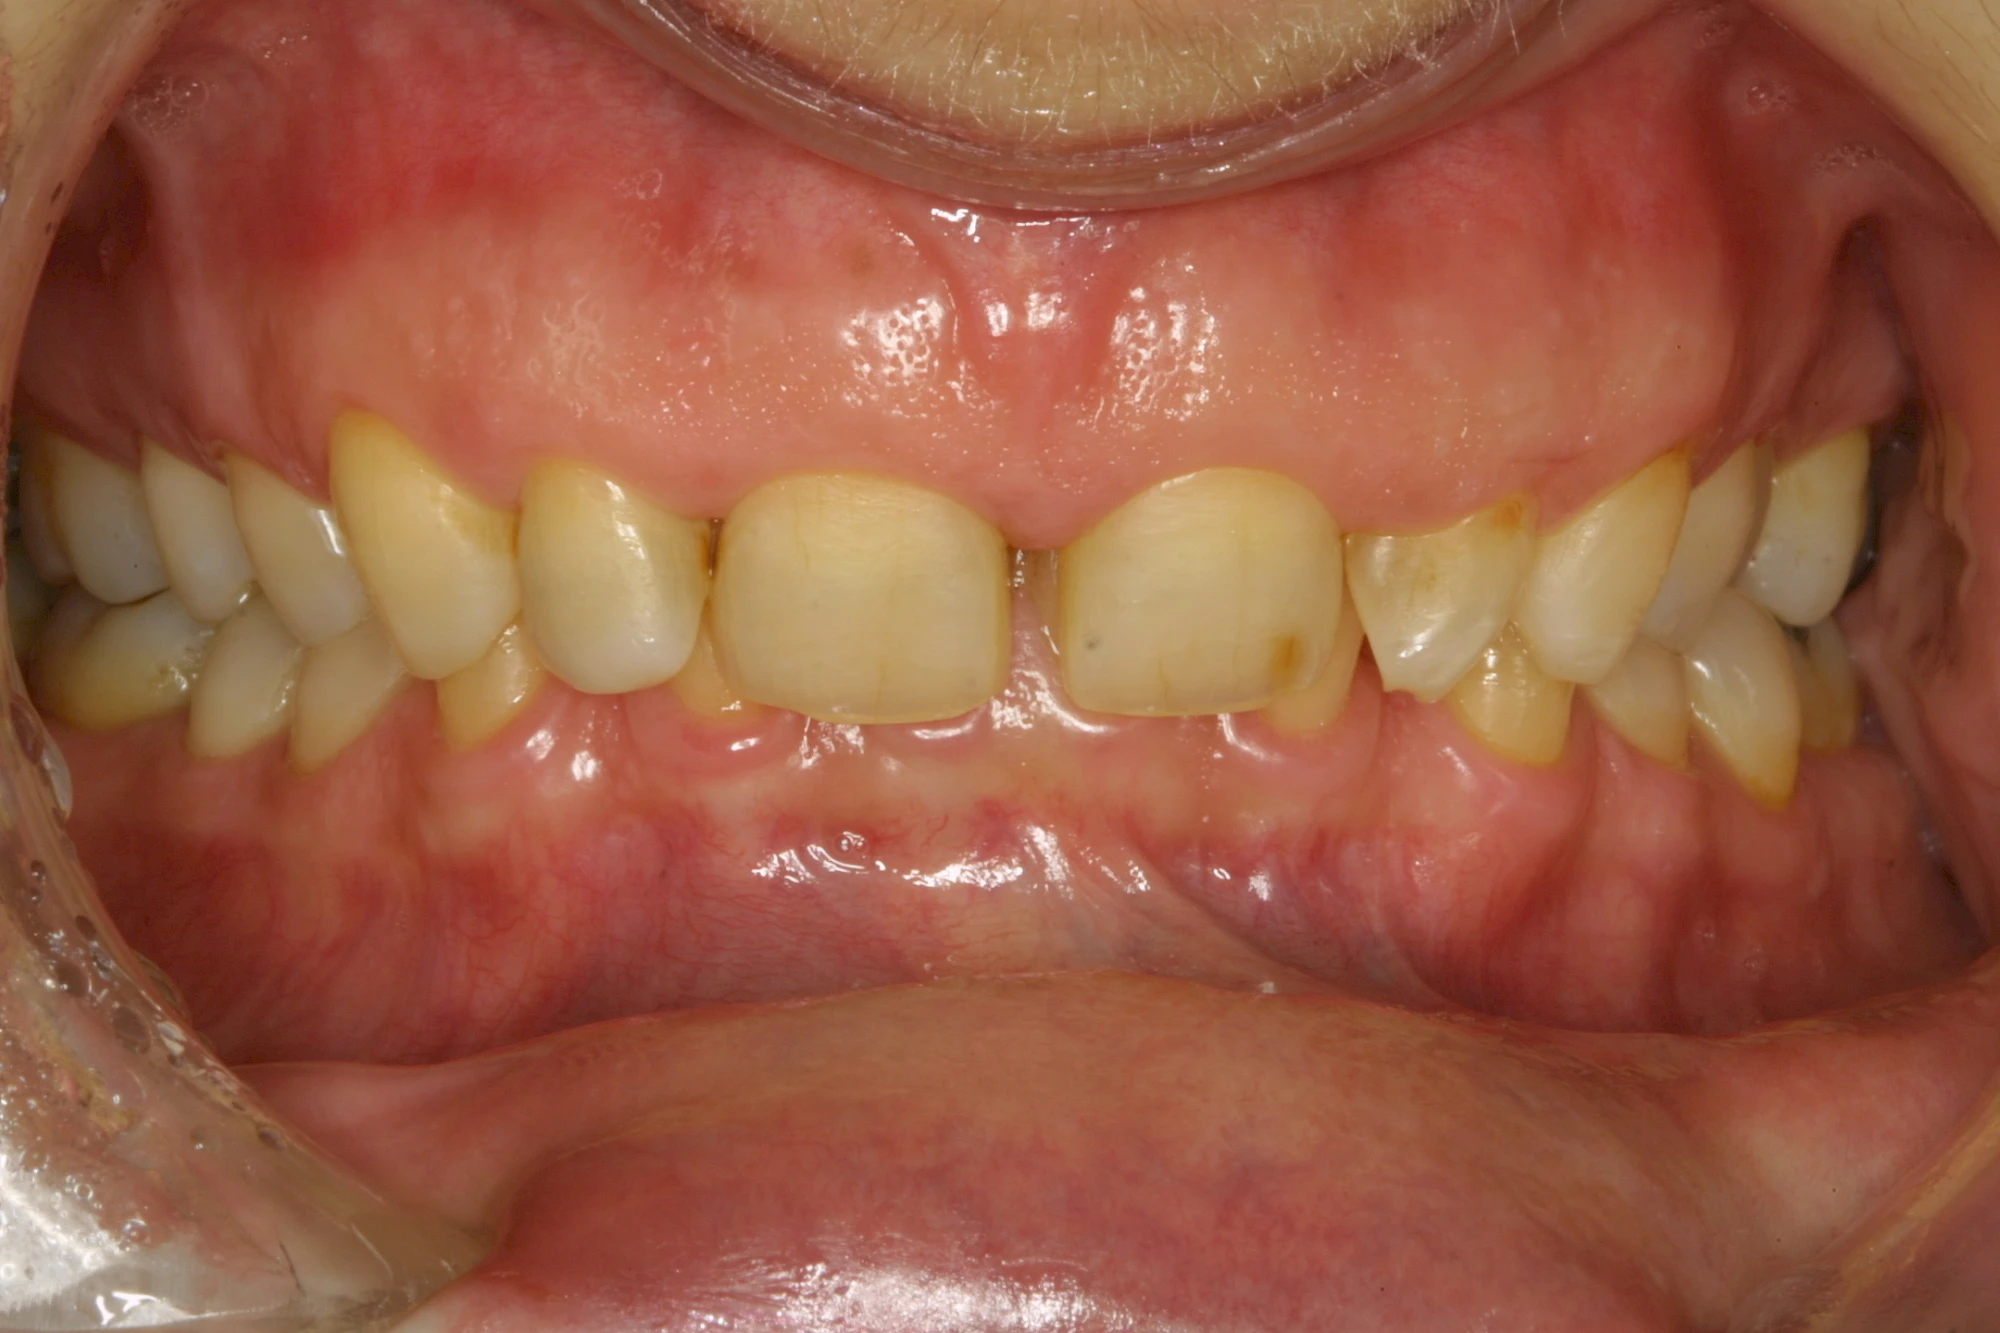

Über die Zeit können verschiedene Prozesse die Zahnhartsubstanzen aufzehren:

- Abnutzung durch Kauen (Abrasion) oder duch durch übermäßiges Knirschen bzw. Pressen (Attrition)

- Säurebedingte Auswaschung (Erosion)

- Knirschen bzw. Pressen und ungünstige Putztechnik (Druck): keilförmige Defekte

Die Zähne können dabei auf Reize (warm, kalt, süß, sauer) oder auch beim Zähneputzen empfindlich oder schmerzhaft sein. In allen diesen Fällen ist es sinnvoll, den Zahnarzt zu kontaktieren und das weitere Vorgehen abzustimmen.

Auswaschung (Erosion) dagegen ist eine Verschleißerscheinung der Zähne aufgrund von immer wiederkehrenden Säureangriffen durch die Nahrung, verstärkt zum Beispiel durch den Genuss säurehaltiger Getränke oder Speisen. Auch bei Menschen mit einer Essstörung (z. B. Bulimie) können die Zähne durch die Magensäure ausgewaschen erscheinen.